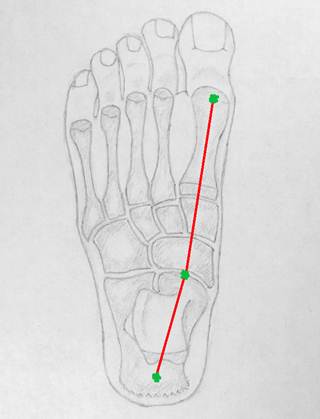

Нормальная

стопа под нагрузкой в виде сверху, её

изображение совмещено с изображением скелета. Красная линия обозначает ось

стопы, зеленые точки обозначают опорные точки, через которые ось стопы

проходит: центр пяточного бугра, центр таранно – ладьевидного сустава и головку

первой плюсневой кости.

Вы

можете заметить минимальную, в несколько градусов, вальгусную деформацию оси,

что является нормальным явлением.

Внутренний край стопы, который отражает состояние её оси в прямом виде,

остается ровным. Это свидетельствует о нормальной форме оси стопы в прямом

виде.